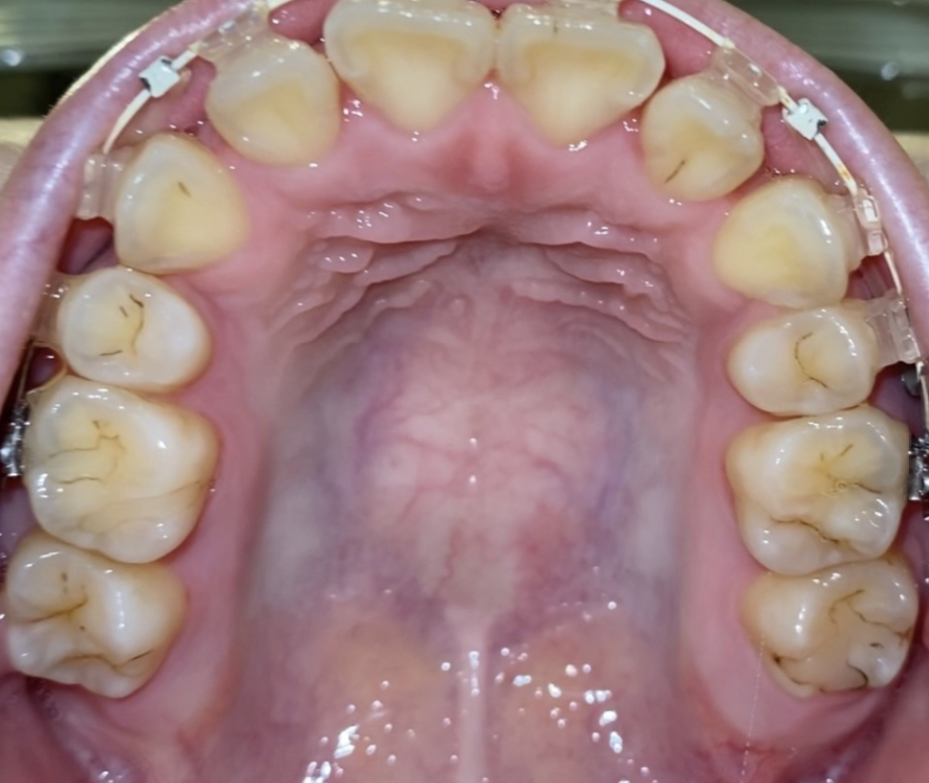

矯正治療中ですが、詰め物の周りが黒くなっているのが気になります。